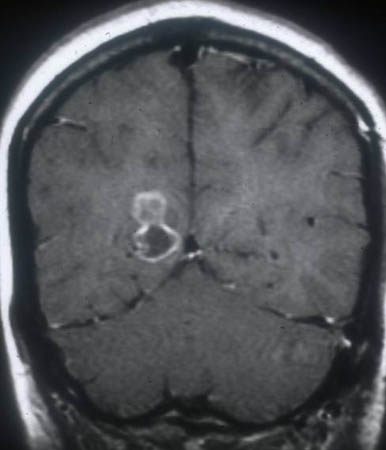

Granular stage - neurocysticercosis: MRI scan showing enhancing lesion without perilesional oedema

From the personal collections of Dr Christina Coyle and Dr Maheen Saeed; used with permission